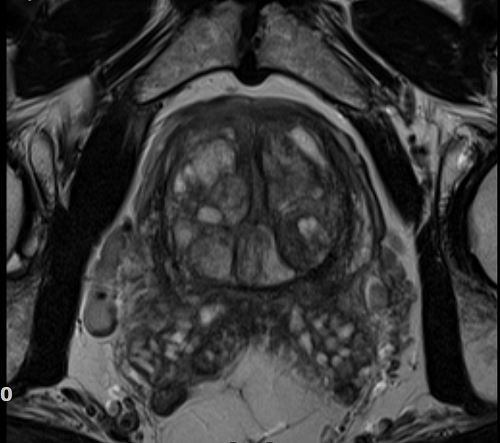

Magnetska rezonancija prostate

Posljednjih nekoliko godina zahvaljujući razvoju tehnologije magnetska rezonancija (MR) dovodi do revolucije u dijagnostici raka prostate te kulminira izmjenama smjernica dijagnostike raka prostate Europskog urološkog udruženja (EAU).

MR bi se u muškaraca s indikacijom za biopsiju prostate praktički trebao učiniti prije same biopsije, a osobito u onih koji su već imali jedan negativan nalaz biopsije. Kako bi MR bio adekvatno izveden članovi EAU i Američkog udruženja radiologa (ACR) preferiraju pregled prostate na MR uređajima snage 3 Tesle dok su uređaji snage od 1,5 Tesla rezervirani za muškarce s implantatima koji nisu kompatibilni s MR od 3T ili za one s implantatima koji svojom pozicijom mogu utjecati na kvalitetu slike (npr. implantati u području kuka).